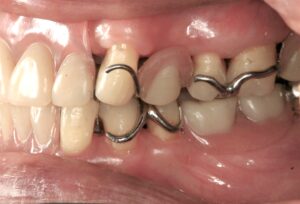

まず、保険のクラスプ義歯がどのような構造かをおさらいします。一般的なクラスプ義歯は、残っている歯に「クラスプ」と呼ばれる金属のバネを引っ掛けて入れ歯を支えます。

抜けた歯を補うために、歯ぐきと同色のプラスチックに人工の歯をつけ、その横に金属のクラスプが付く、という形です。

問題は、クラスプが歯にただ引っ掛けられているだけのため、硬いものを噛むと多少のがたつきが起こり、横からのねじれに弱い点です。

その結果、食べ物が挟まりやすく、噛むたびに支えている歯が揺さぶられます。入れ歯を外すときにも歯がさまざまな方向に揺れるため、歯に負担がかかるのです。